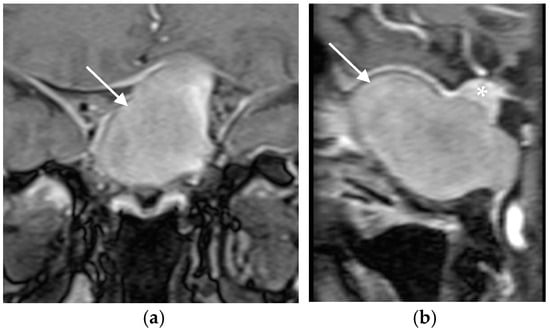

The patient underwent transsphenoidal debridement of the lesion. The material was removed from the sella, and bone erosion was noted during the procedure. Histopathological examination of formalin-fixed, paraffin-embedded tissue stained with hematoxylin and eosin (H&E) confirmed the presence of fungi (Figure 2a). Grocott Methenamine Silver staining revealed fungal hyphae (Figure 2b). There was no evidence of fungal tissue invasion, pituitary adenoma, or other pre-existing pituitary lesions.

Postoperatively, the patient experienced significant improvement in headache and normalization of vision and visual fields. The patient in this case was treated exclusively with surgery, without a postoperative antifungal therapy. She was cured by surgery alone. Follow-up examinations at three months and one year post-surgery demonstrated a complete resolution of symptoms without disease recurrence (Figure 3). Pituitary function remained intact, and no additional therapy was required. The patient was followed for three years postoperatively with annual MRI scans, which showed no signs of FS or pituitary lesions.

Figure 2. (a) The sellar content obtained during the transphenoidal operation stained by Haematoxylin and Eosin (H&E × 250). (b) The fungal hyphae within the sellar content (Grocott Methenamine Silver × 250) confirmed the fungal etiology.

Figure 3. Coronal MRI scan of the sellar region after the operation showing a complete resolution of the pathological process and a normal pituitary gland (marked with white arrow).